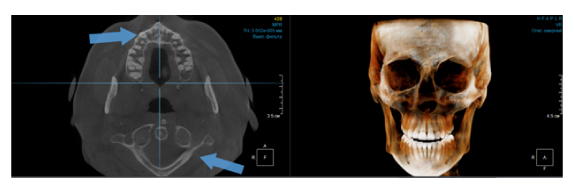

Когда мы отправляем пациента на проведение рентгенологического исследования, то подвергаем его определенному риску. Именно это нужно осознавать, так как в радиологии нет минимально безопасной дозы, поэтому любое назначение должно быть обоснованным. В связи с этим поле обзора является достаточно принципиальным параметром. Если вы врач-терапевт, занимающийся эндодонтией или ортопед, который решил оценить состояние зубов перед протезированием, то вы должны понимать, что проведение исследования с полем обзора 10x10 см будет гораздо информативнее нежели большие снимки (18x16 см и выше). В первую очередь это связано с размером вокселя, о нём я напишу чуть ниже, а второе это то, что вам придется увеличивать изображение по каждому корневому каналу, и от этого вы будете терять в качестве снимка (рис. 1). И ситуация наоборот, если вы ортодонт, то чтобы использовать весь диагностический потенциал, а также возможность загрузить данные для расчёта 3D цефалометрии, то вам нужны снимки, захватывающие весь лицевой отдел черепа. Таким образом, дентальный томограф должен обладать возможностью проведения исследований с разным FOV, обеспечивая нужды всех специалистов. Если ваша клиника базируется на терапевтическом, хирургическом и ортопедическом приёме, то на мой взгляд, можно рассмотреть дентальные томографы с полем обзора 10x10 см или 16x10 см. Последний больше актуален для тех, кто работает с ВНЧС, так как антропометрически в 16 см даже у брахицефалов сустав должен попадать.  Если в клинике есть ортодонтическое направление, функциональная стоматология, ЛОР-практика или ЧЛХ, то, безусловно, вышепредставленные снимки не будут отражать всех данных, которые необходимы для диагностики и планирования лечения. Здесь лучше рассмотреть конусно-лучевые компьютерные томографы с зоной сканирования 18x16 или 20x20 см. Особо стоит отметить понятие «сшивки». Есть дентальные томографы, которые делают один цельный снимок размерами, которые описаны выше, а есть аппараты, которым нужно провести две экспозиции и сшить изображения вместе, чтобы получился необходимый объём исследования. Как правило, вторые томографы чуть дешевле, но всё зависит от того, насколько вам нужна максимальная точность исследования. Если при сшивке челюсти и зубы, как правило, совмещаются практически идеально, то на уровне позвоночного столба происходит наслоение тканей и от него уже не избавиться (рис. 2). Второй отрицательный момент – это износ оборудования, логично, что он будет быстрее, так что экономия средств — это ещё спорный вопрос.

Рис. 1. Представлены два исследования (10x10 см и 20x20 см). На обоих изображениях хорошо видна канально-корневая система зубов, но, если масштабировать второе исследование, то качество неминуемо снизится, как и диагностическая эндодонтическая эффективность.